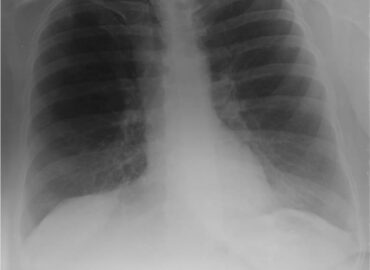

Octubre 2025. Conci Carpinella

Masculino 75 años, APP: TBC, MC: Tos productiva crónica y disnea.